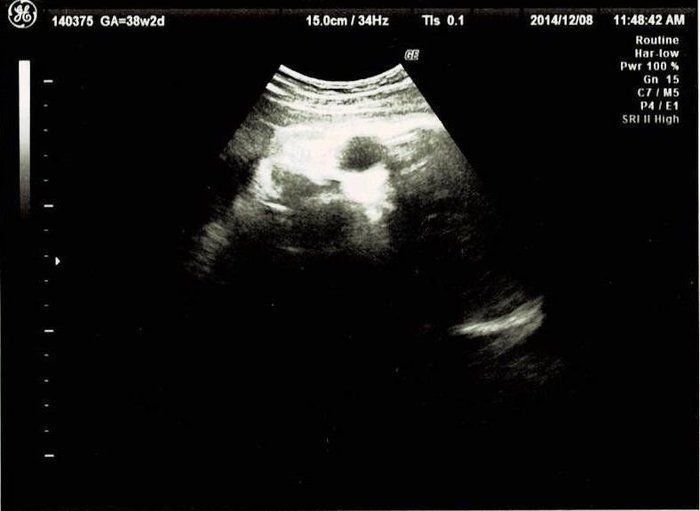

クリコさんの妊娠38週目のエコー写真

このころ、ママ友から続々と「出産しました」メールが届き始めました。10時間以上陣痛に苦しんだり、産後あちこちに痛みが出たりと、リアルな情報にドキドキもしましたが、「トイレは前かがみがいい」とか、「円座クッション、授乳クッションがあるといい」など、産後にかなり役に立つ情報も得られて心強かったです。診察では全く赤ちゃんが降りてくる気配がなく、そろそろ生まれてほしいと思うように。